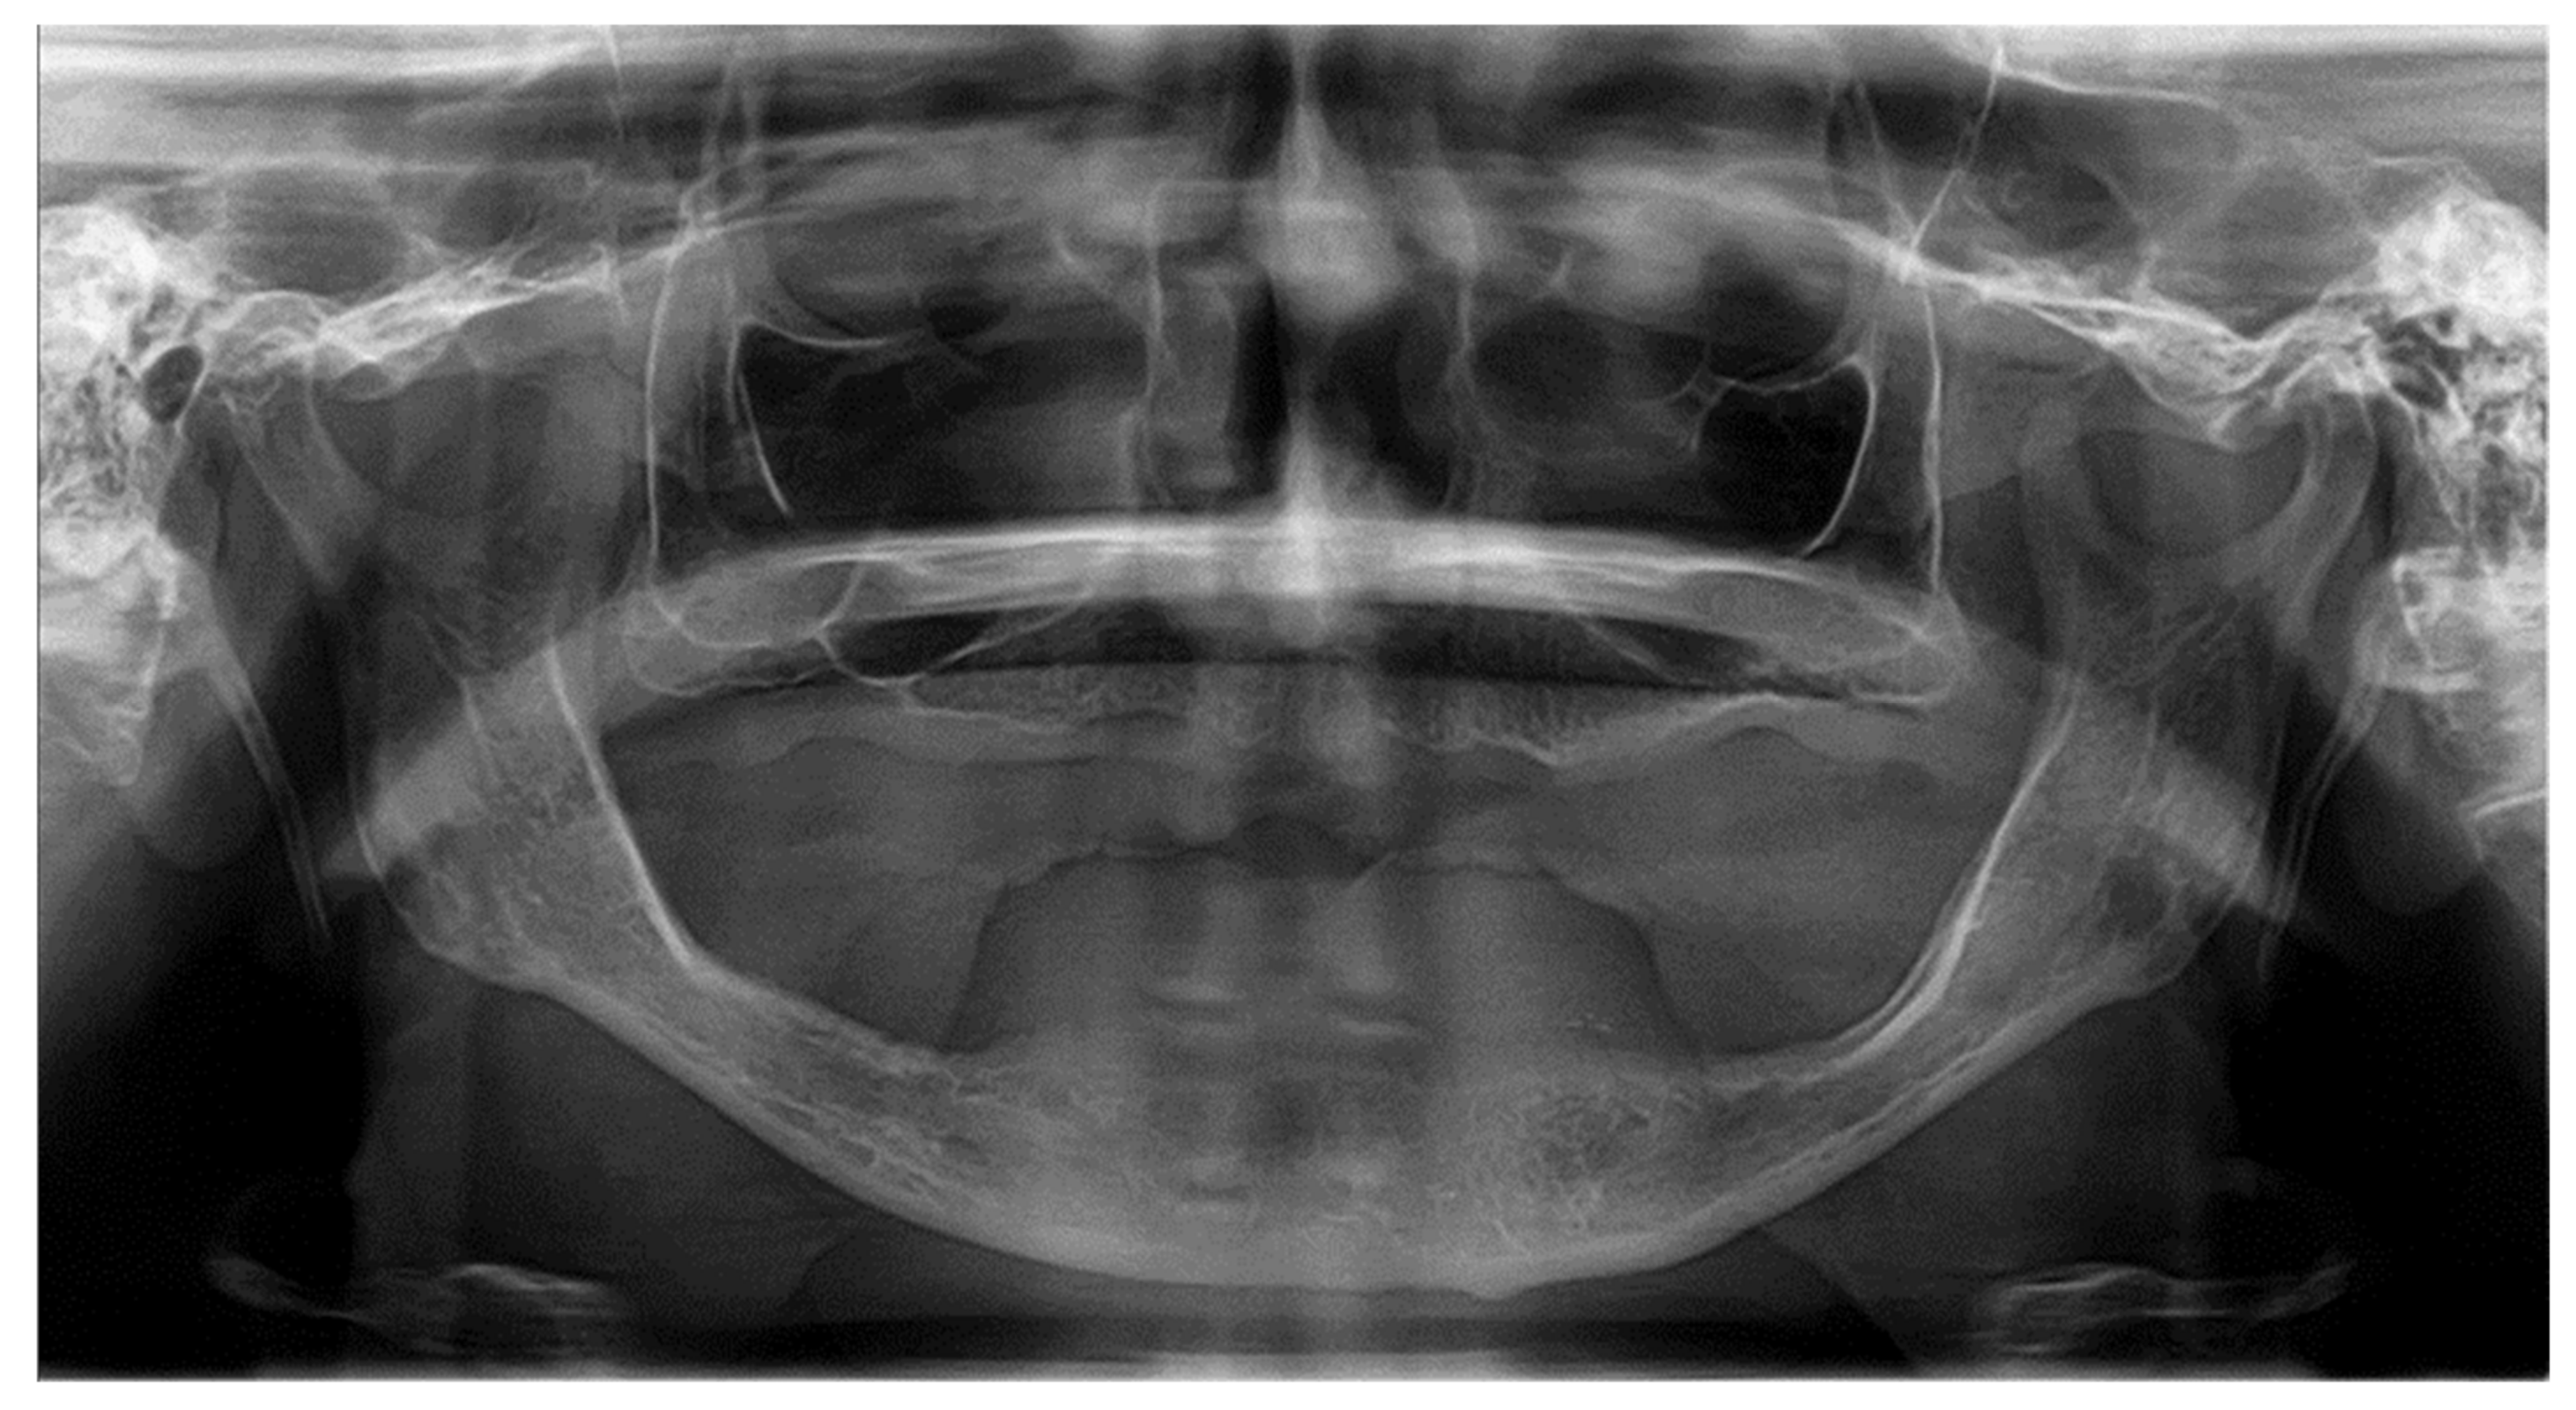

2.2. Clinical Case Vignettes

2.4. Description of the Clinical Case Vignettes